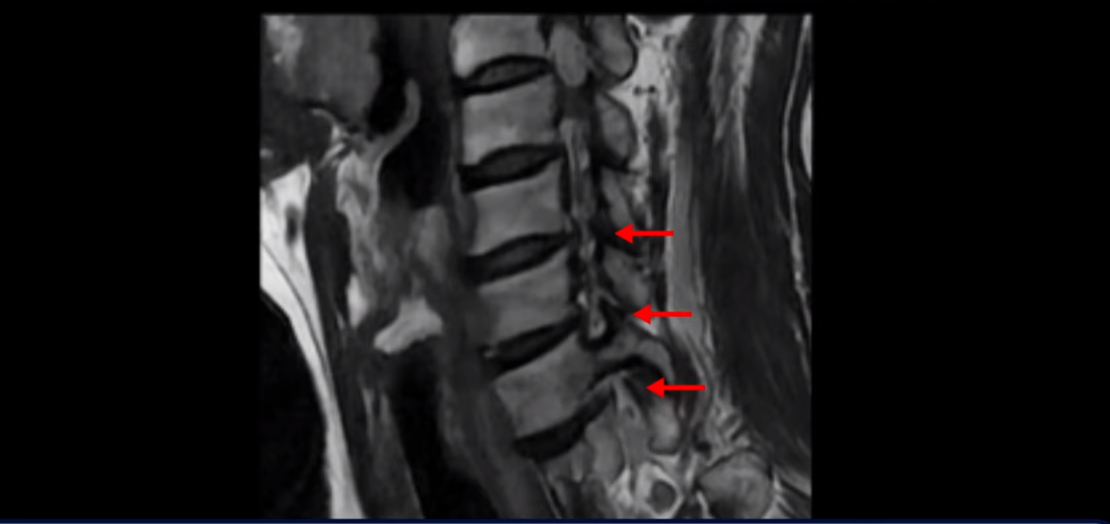

이분 MRI를 보면 세 마디의 퇴행성 목디스크가 있습니다. 4번 5번, 5번 6번과 6번 7번이 세 마디인데

디스크 파열은 4번 5번이 제일 심합니다.

그런데 이 환자분의 방사통은 왼쪽 어깨와 팔입니다. 그래서 이 4번 5번 디스크 파열은 왼쪽 방사통의 원인이 아닌 걸로 보입니다. 6번 7번을 보면 디스크가 왼쪽으로 밀려 나와 있고, 뼈도 자라나 있습니다.

이렇게 뼈가 자라나 있으니까, 신경가지가 빠져나가는 추간공을 보면 여러 마디가 다 좁아져 있습니다.

이런 걸 협착이라고 합니다. 목이 협착이 진행된 것이죠. 그런데 왜 목디스크, 목 협착 치료가 허리보다 훨씬 더 쉽고 빠르다고 하는 걸까요? 그 이유는 목은 하중을 허리보다 훨씬 더 적게 받기 때문입니다. 하중을 적게 받으니까 신경 눌림이 조금만 줄어도 증상이 훨씬 더 빠르게 좋아지는 것입니다.